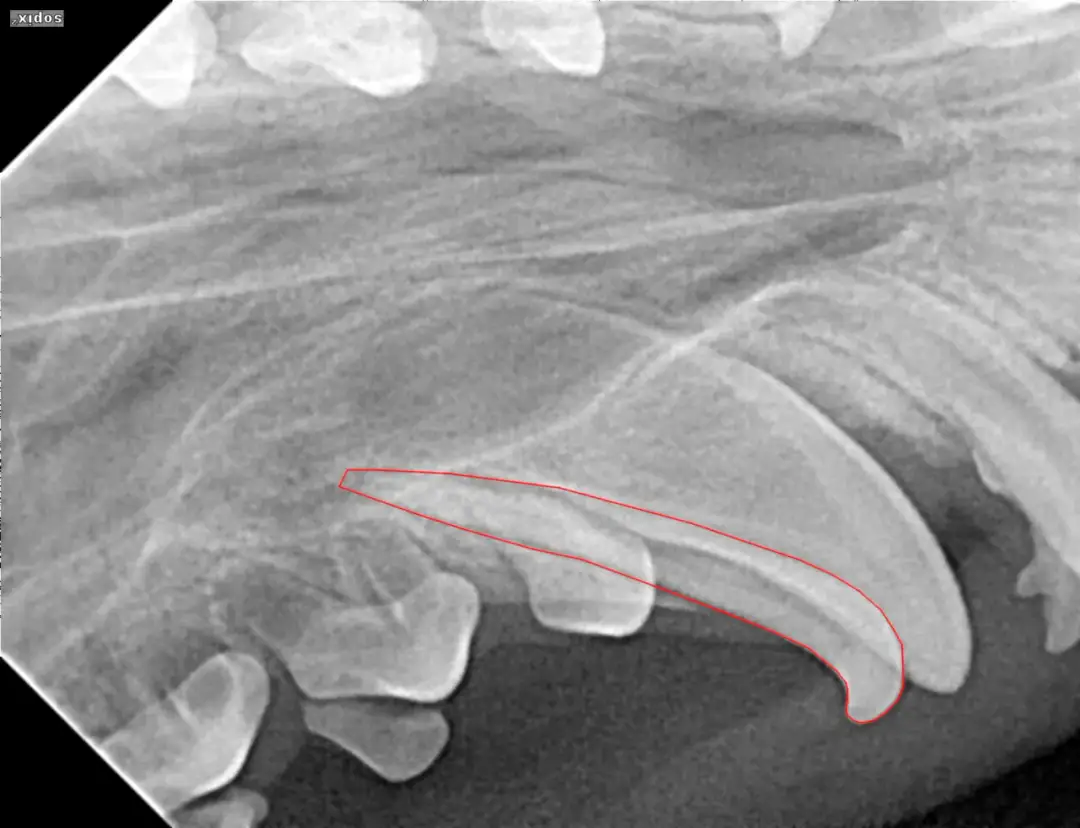

Przetrwałe zęby mleczne u psa? Dowiedz się, kiedy usunąć "rekinie zęby", jakie są zagrożenia i jak wygląda bezpieczny zabieg. Nie ignoruj problemu!